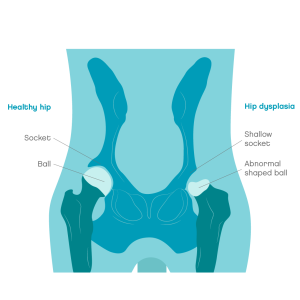

Homeopathic remedies for hip dysplasia best sale

Homeopathic remedies for hip dysplasia best sale, Hip Dysplasia Causing Osteoarthritis Pain in a Cat best sale

Product code: Homeopathic remedies for hip dysplasia best saleHip dysplasia in dogs Joii Pet Care best sale, Hip pain Mann Homeopathy Clinic Rajkot best sale, Amazon Maxwell Pet by Dr.Garber Hip Joint for Dogs The First Natural Biotherapy Supplement Drops to Support and Restore Hip Joint Health Repair and Ease Hip Joint best sale, Homoeopathic Remedies For Arthritis In Dogs Stem Cell Vet best sale, Hip Dyspasia in Dogs best sale, Hip Dysplasia efc homeopathy best sale, Rescue Remedy Natural Homeopathic Stress Relief Drops For Pets 20 ml Amazon Pet Supplies best sale, Homeopathic treatment of Hip Displasia in a Dog by Sarah Stieg DVM MRCVS and Lisa Melling DVM CVH Pitcairn Institute of Veterinary Homeopathy best sale, 8 Simple Home Remedies for Hip Pain Phyiostattva best sale, Rescue Remedy Natural Homeopathic Stress Relief Drops For Pets 20 ml Amazon Pet Supplies best sale, 15 Dog hip dysplasia ideas dog hip dysplasia dog remedies hip dysplasia best sale, Hip Dysplasia In Dogs best sale, Walk Easy Cat Dog Joint Pain Relief Effective Cat Pain Reliever Anti Inflammatory Natural Dog Hip and Joint Supplement Helps with Mobility best sale, Hip Dysplasia in dogs Goel Vet Pharma best sale, Is There a Natural Cure for Hip Dysplasia International Hip Dysplasia Institute best sale, You Can Treat Your Dog s Hip Dysplasia Naturally Healing Paws Center Fort Lauderdale FL best sale, Homeopathic remedies for hip flakier dysplasia in dogs best sale, Amazon T Relief Extra Strength Arthritis Pain Reliever Arnica 12 Natural Medicines for Joint Soreness Stiffness Aches Quick Dissolving Pain Relief for Women Men 100 Tablets Health Household best sale, Developmental Dysplasia of the Hip Homeopathic Remedies best sale, Dog Pain Relief Natural best sale, T Relief Pet Pain Relief Arnica 12 Powerful Natural Medicines Help Reduce Muscle Joint Hip Pain Soreness Stiffness Injuries in Dogs Cats best sale, Top 5 Remedies For Dog Joint Pain And Injury best sale, How To Treat Hip Bursitis Orthobridge Orthopaedic Institute best sale, Buy Dysomin Drops Homeopathic Medicine Doctor Bhargava best sale, JointButter Dr. Dobias Natural Healing best sale, Beyond the Itch Exploring Homeopathic Remedies for Dog Skin Allergies Goel Vet Pharma Pvt. Ltd. Beyond the Itch Effective Homeopathic Remedies for Dog Skin Allergies best sale, Cat Arthritis Meds best sale, How To Treat Hip Bursitis Orthobridge Orthopaedic Institute best sale, Natural Remedies For Hip Dysplasia best sale, Hip Dysplasia and Everyday Life International Hip Dysplasia Institute best sale, Homeo Treatment for Hipdysplasia Hipdysplasia in dogs best sale, Ruta graveolens a useful homeopathic medicine for musculoskeletal disorders ScienceDirect best sale, T Relief Pet Pain Relief Arnica 12 Powerful Natural Medicines Help Reduce Muscle Joint Hip Pain Soreness Stiffness Injuries in Dogs Cats best sale, Hip Dysplasia Causing Osteoarthritis Pain in a Cat best sale, Hip Dyspasia in Dogs best sale.